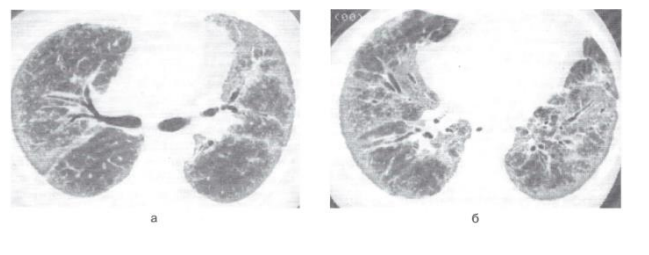

Doctors usually call lung damage "frosted" glass or consolidation.

This occurs due to the fact that the vessels and alveoli break the barrier and the alveoli of the lungs are filled with fluid from the vessels.

Not all the alveoli in the "frosted glass" zone are completely filled with liquid, but gas exchange is difficult, so it becomes difficult to breathe.

The diagnosis is made by a PCR smear from the nose, (if the material is found in the RNA of the coronavirus) + test for antibodies to Covid-19. Sometimes based on a typical picture of viral pneumonia in a chest CT scan. Changes in the lungs in viral pneumonia are poorly visible on a regular x-ray.

The radiological picture is usually characterized by a unilateral interstitial lesion in the form of pneumonitis, or bilateral focal drain pneumonia.

My Opinion of an Expert Clinical Pharmacist is that it is pneumonitis

Pneumonitis is an inflammation of the alveolar walls and interstitial lung tissue, in this case of infectious origin, which leads to scarring of the alveoli and fibrous changes in the supporting structures of the lungs.

The difference between pneumonitis and pneumonia is clearly visible on x-rays.

With pneumonitis, the pulmonary pattern is enhanced, darkening is observed in the lower part of the lungs, with pneumonia - darkening foci have uneven contours in various parts of the lungs.

Pneumonia is still an incorrect term, patients with COVID-19 develop virus-induced interstitiopathy (pneumonitis).

With pneumonitis, the pulmonary pattern is enhanced, darkening is observed in the lower part of the lungs, with pneumonia-darkening foci have uneven contours in various parts of the lungs.

Those changes that are detected in the lungs with covid are not true pneumonia. On a CT scan, the doctor sees a "frosted glass" - a decrease in the transparency of the lung tissue with a visible pattern of blood vessels and bronchi. This is due to a decrease in the airiness of the alveoli and thickening of the walls.

Two x-rays of the woman's chest.

The images show white spots in the lower corner of her lungs, which indicate what radiologists call «opaque frosted glass».

X-ray of the patient's chest. The difference between the images is 3 days.